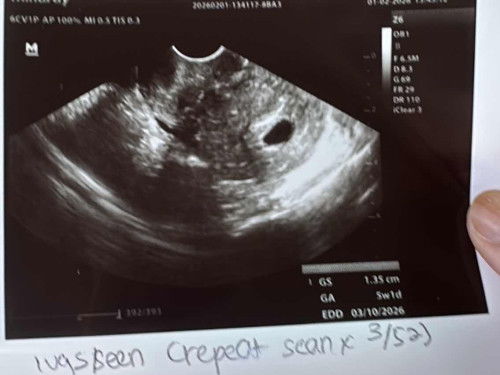

Saya cirit birit dari awal mengandung sampai sekarang tapi ada masa najis okay ada masa cair. Sehari tu paling banyak pun 3 kali tapi bukan setiap hari. Normally sekali je cirit. Saya memang susah minum air. Makan pun sikit. Sejak kena gastrik teruk masa awal hanil tu saya jadi kurang nak makan. Makan lebih je bloated. Saya pula nak demand2 suami pun suami baru dapat keje yang gaji kena downgrade disebabkan komitmen tinggi saya makan je apa ada. Result urine pagi mild anemia je. Plus now saya baru nak tukar pada iberet punya vitamin. Supposedly harini dapat multivitamin and ors tapi maybe doc lupa bagi. And.. sebabkan cirit lama lebih sebulan, doc suruh ambil sample darah and najis utk check further. Ada tak yg pengalaman macam saya? Saya takut nak warded :'( #Needadvice #ciritbirit #trimester1 #mohonbantujawabbunda #11weeks